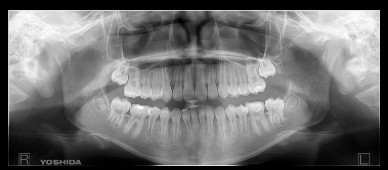

ortopantomografia - Clinica Uribe

Otros > rayos X digital

CON UNA SOLA TOMA NOS ENSEÑATODA SU BOCA Y PODEMOS OBSERVAR PROBLEMAS O LESIONES OCULTAS.